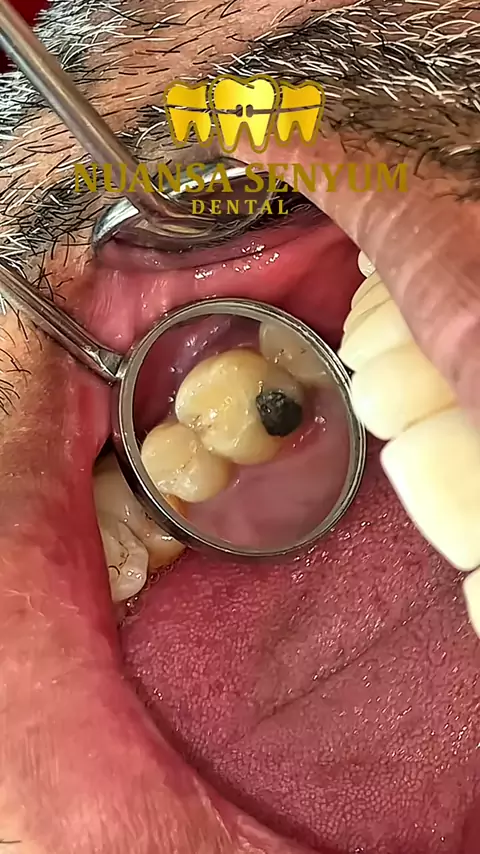

Perawatan syaraf sisa akar dan pemasangan gigi palsu untuk mengembalikan fungsi dan estetika 😃 Dengan perawatan syaraf yang tepat dan pemasangan gigi palsu, senyum bisa kembali utuh dan percaya diri. Percayakan perawatan gigi anda di Klinik Nuansa Senyum Dental 🦷✨. Reservasi di : 081 90 900 6161 #nuansasenyumdental #doktergigisurabaya #perawatansaluraakar ゚viral

Assalamu'alaikum Senyumers🤗, Meski tersisa satu, gigi tetap punya harapan. Perawatan syaraf membantu menghilangkan nyeri dan mempertahankan gigi asli selama mungkin 🦷✨ Yuk Reservasi Sekarang Juga di: 081 90 900 6161 #nuansasenyumdental #doktergigisurabaya #perawatansaluraakar ゚viral

GIGI GRAHAM BOLONG 😱😱 Assalamualaikum senyumers🤗, Kalok gigi bolong gede gitu diapaain sih? Harus dilakukan perawatan syaraf ya senyumers😁. Jangan bingung mau perawatan syaraf dimana? Yukkk ke Nuansa Senyum Dental aja yg pastinya dikerjakan dengan alat canggih dan dokter yang ahli dalam penanganan perawatan saluran akar. Reservasi di: 081 90 900 6161 #nuansasenyumdental #doktergigisurabaya #perawatansaluranakar ゚viral

Perawatan saluran akar nihh,, siapa yang gigi nya kalau malam suka nyut nyut an atau sakit dan mik obat sakit g ilang2.. ati2.. itu uda ken syaraf lubang giginya.. tp tenang aja,, bawa ke NSD aja.. dg dokter yg berpengalaman dan alat2 yg super canggih di kami semua bisa di atasi..😎😎🙏😍 Audio real !! #nuansasenyumdental #nsd #perawatansaluraakar